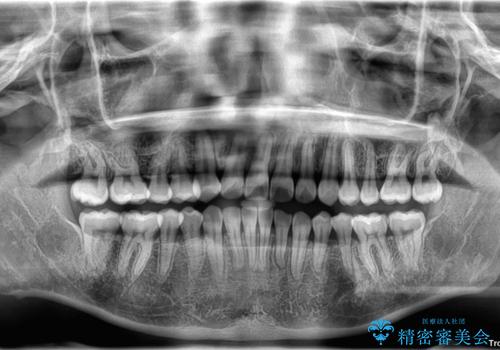

初診時、上下顎ともに歯列の不正が認められ、特に左下の小臼歯が大きく歯列から外れている状態でした。その影響により、下顎の正中が左側へシフトしており、見た目だけでなく噛み合わせにも影響が出ていました。

左下の小臼歯をきれいに歯列内へ並べるためには、まず十分なスペースの確保が必要でした。

そこで本症例では、上顎右側にアンカースクリュー(矯正用インプラント)を埋入し、そこからゴムかけ(顎間ゴム)を行うことで、下顎の正中を右方向へコントロール。

これにより、左下小臼歯がく並ぶためのスペースを確保することができました。